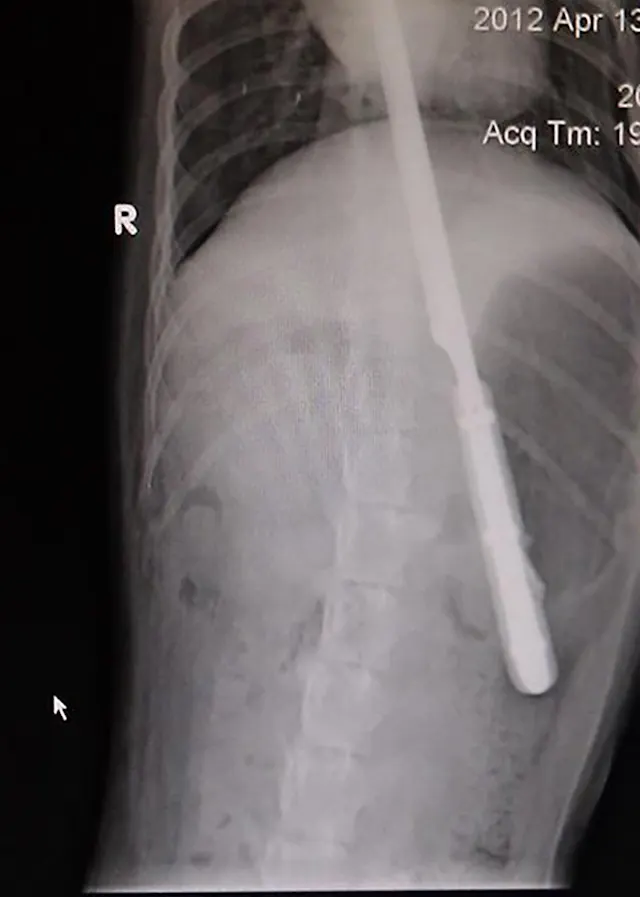

"This energetic 10-month-old Labrador swallowed a 12-inch serrated knife. The puppy was bouncing off the walls when he was brought in and it was hard to keep him still. Surgery went well and amazingly, nothing was damaged!"—Katelyn E